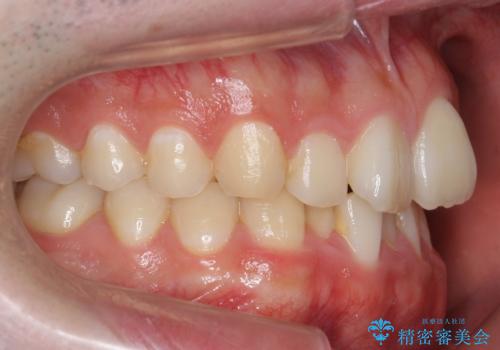

前歯のがたつき・すれちがい咬合を非抜歯で。流行の、格安マウスピースでは難しい、ワンランク上の治療

- 前歯のがたつきを主訴に来院。

左下の奥歯を後ろに移動して、中に入ってすれちがっていた小臼歯を並べました。

巷(ちまた)で大きく宣伝している某 格安マウスピース矯正では、奥歯を後ろに動かすことはできないです。